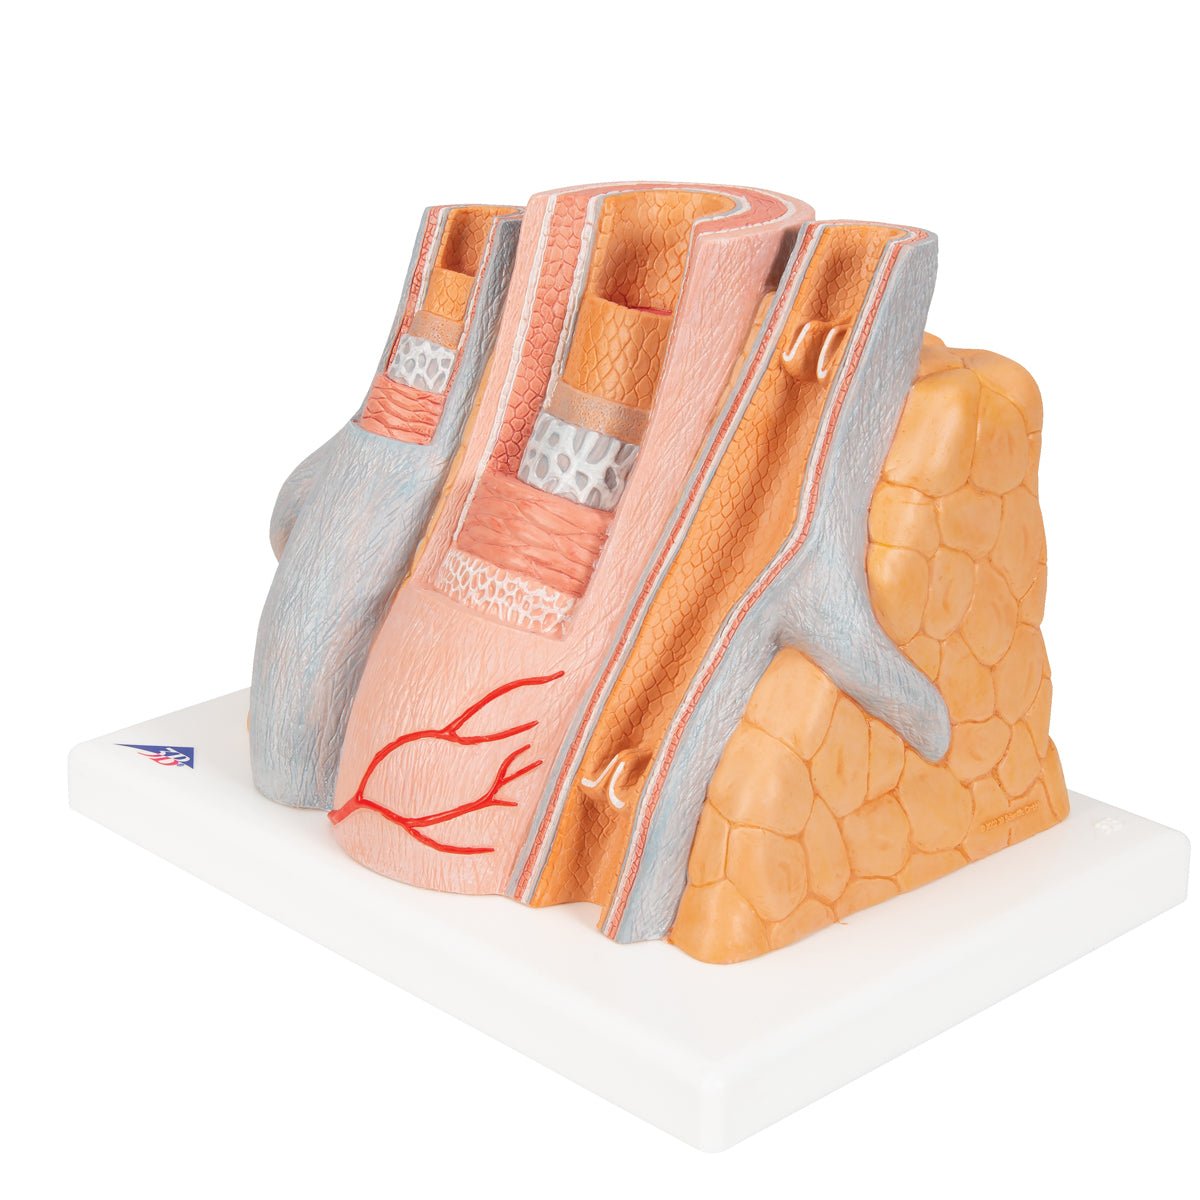

Salg af anatomiske modeller er det bærende element i eAnatomi, selvom vi også bruger mange ressourcer på at udvikle vores egne anatomiske materialer som fx plakater. Anatomiske modeller anvendes til forskellige formål og kan både vise afgrænset væv, organer samt organsystemer. Søger du en simpel model af knoglevæv eller måske en avanceret torso-model baseret på MRI teknologi, kan du finde det hele på eanatomi.com.